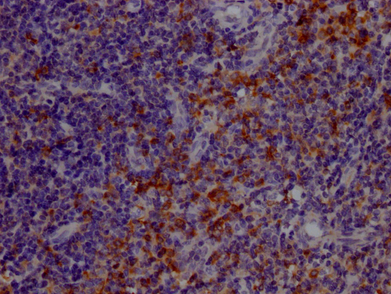

圖:TLR7單克隆抗體(6E5)在1:100稀釋度下對石蠟包埋的人扁桃體組織進(jìn)行IHC染色,實(shí)驗(yàn)在Leica Bond系統(tǒng)上完成。經(jīng)過脫蠟和水化后,抗原修復(fù)通過檸檬酸緩沖液(pH 6.0)在高壓下進(jìn)行。切片用10%正常山羊血清在室溫下封閉30分鐘,然后在4℃下過夜孵育一抗(1% BSA)。一抗通過HRP標(biāo)記的山羊抗兔IgG聚合物檢測,并使用0.05% DAB進(jìn)行顯色。